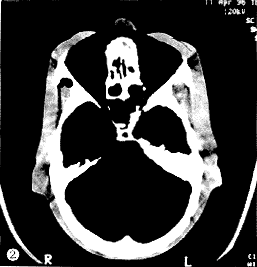

实测表明,中国头颈部体模与中国成人头颅活体相比无显著性差异。中国体模在组织材料的多样性、辐射等效均匀性和实用性优于国外同类的体模(图1~2)。

图1 安装热释剂量计的中国头颅体模CT扫描断层

图2 美国Anderson头颅体模CT扫描断层